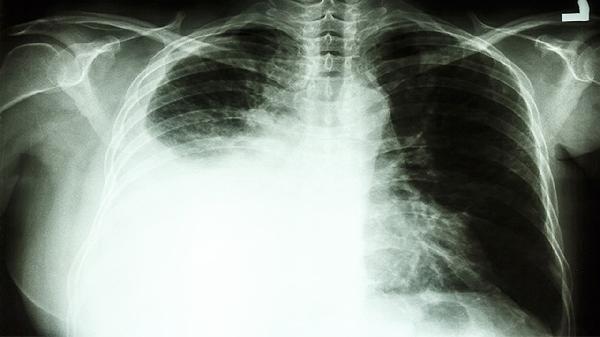

CT检查能清晰显示肺部结节或肿块的形态、大小及位置,对早期肺癌有较高敏感性。薄层CT可发现直径小至2毫米的结节,增强CT还能观察病灶血供情况。磨玻璃样改变、分叶状边缘、毛刺征等影像特征可提示恶性可能,但炎症、结核等良性疾病也可能出现类似表现。临床中约20%的肺结节经病理证实为恶性,其余多为良性病变。

当CT发现可疑病灶时,需进一步通过支气管镜活检、经皮肺穿刺或手术切除获取组织标本。免疫组化检测可明确病理类型,基因检测能指导靶向治疗。PET-CT虽能鉴别肿瘤代谢活性,但仍有假阳性风险。部分特殊类型肺癌如小细胞癌,CT表现可能不典型,需结合痰细胞学检查综合判断。